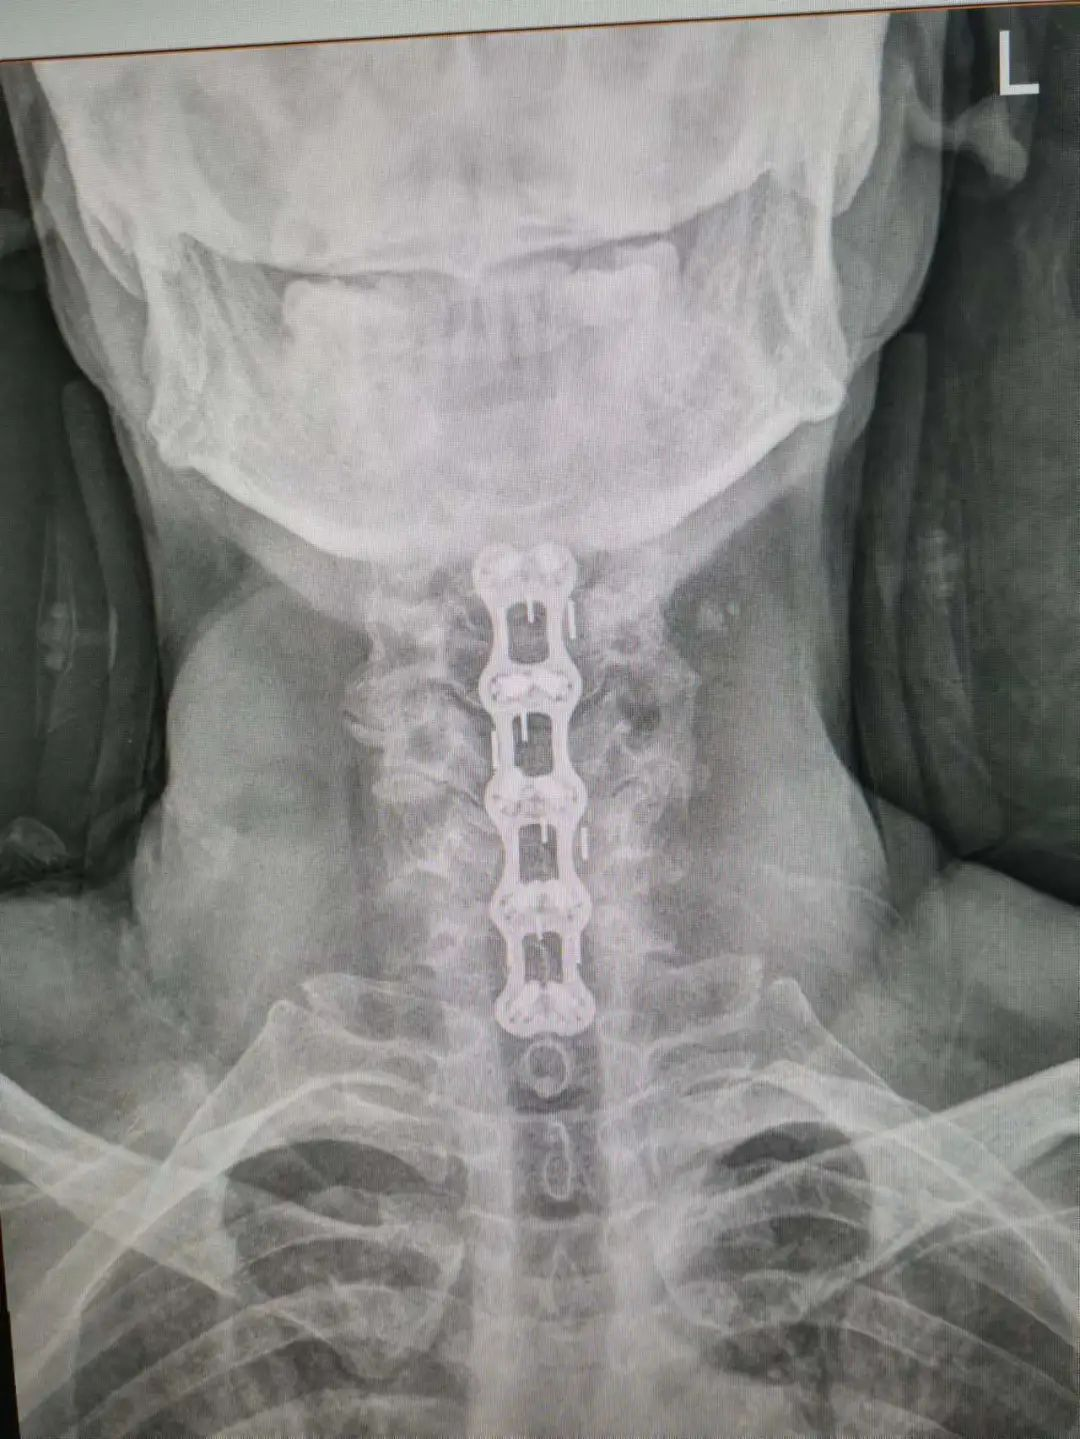

楊先生脊髓性頸椎病拍片

由于楊先生的病情嚴重,需住院治療。楊先生入院后,瀘州市中醫(yī)醫(yī)院骨傷二科科主任楊陳一制定了手術(shù)計劃,決定脊髓型頸椎病的手術(shù)從前路切開減壓,頸3/4 、頸4/5、 頸5/6、 頸6/7椎間盤切除,椎間融合,鋼板內(nèi)固定術(shù)手術(shù),而腰椎管狹窄癥經(jīng)后路切開減壓,腰3/4、腰4/5椎同盤動除,椎間融合、釘棒系統(tǒng)內(nèi)固定術(shù)。